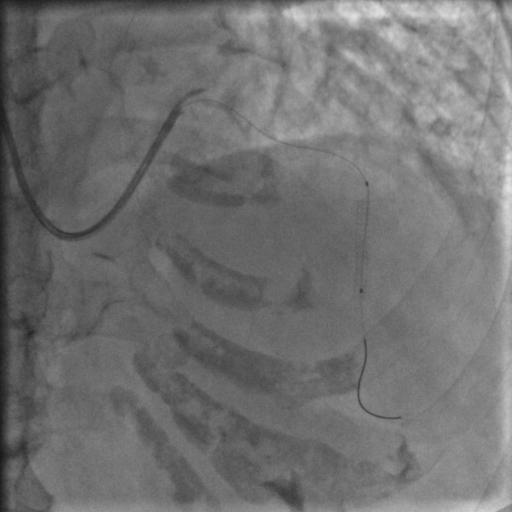

按照常规,更换指引导管,送入导丝,顺利通过闭塞病变到达前降支远端,很顺利,D-to-B时间70分钟,达标,曙光在前头。

图5

导丝过了之后常规造个影:

图6

没通,这个也很正常,急性冠脉闭塞导丝过了之后血栓还堵着是很经常的事,按常规打点欣维宁,考虑到她86岁,打入8ml欣维宁,造影: